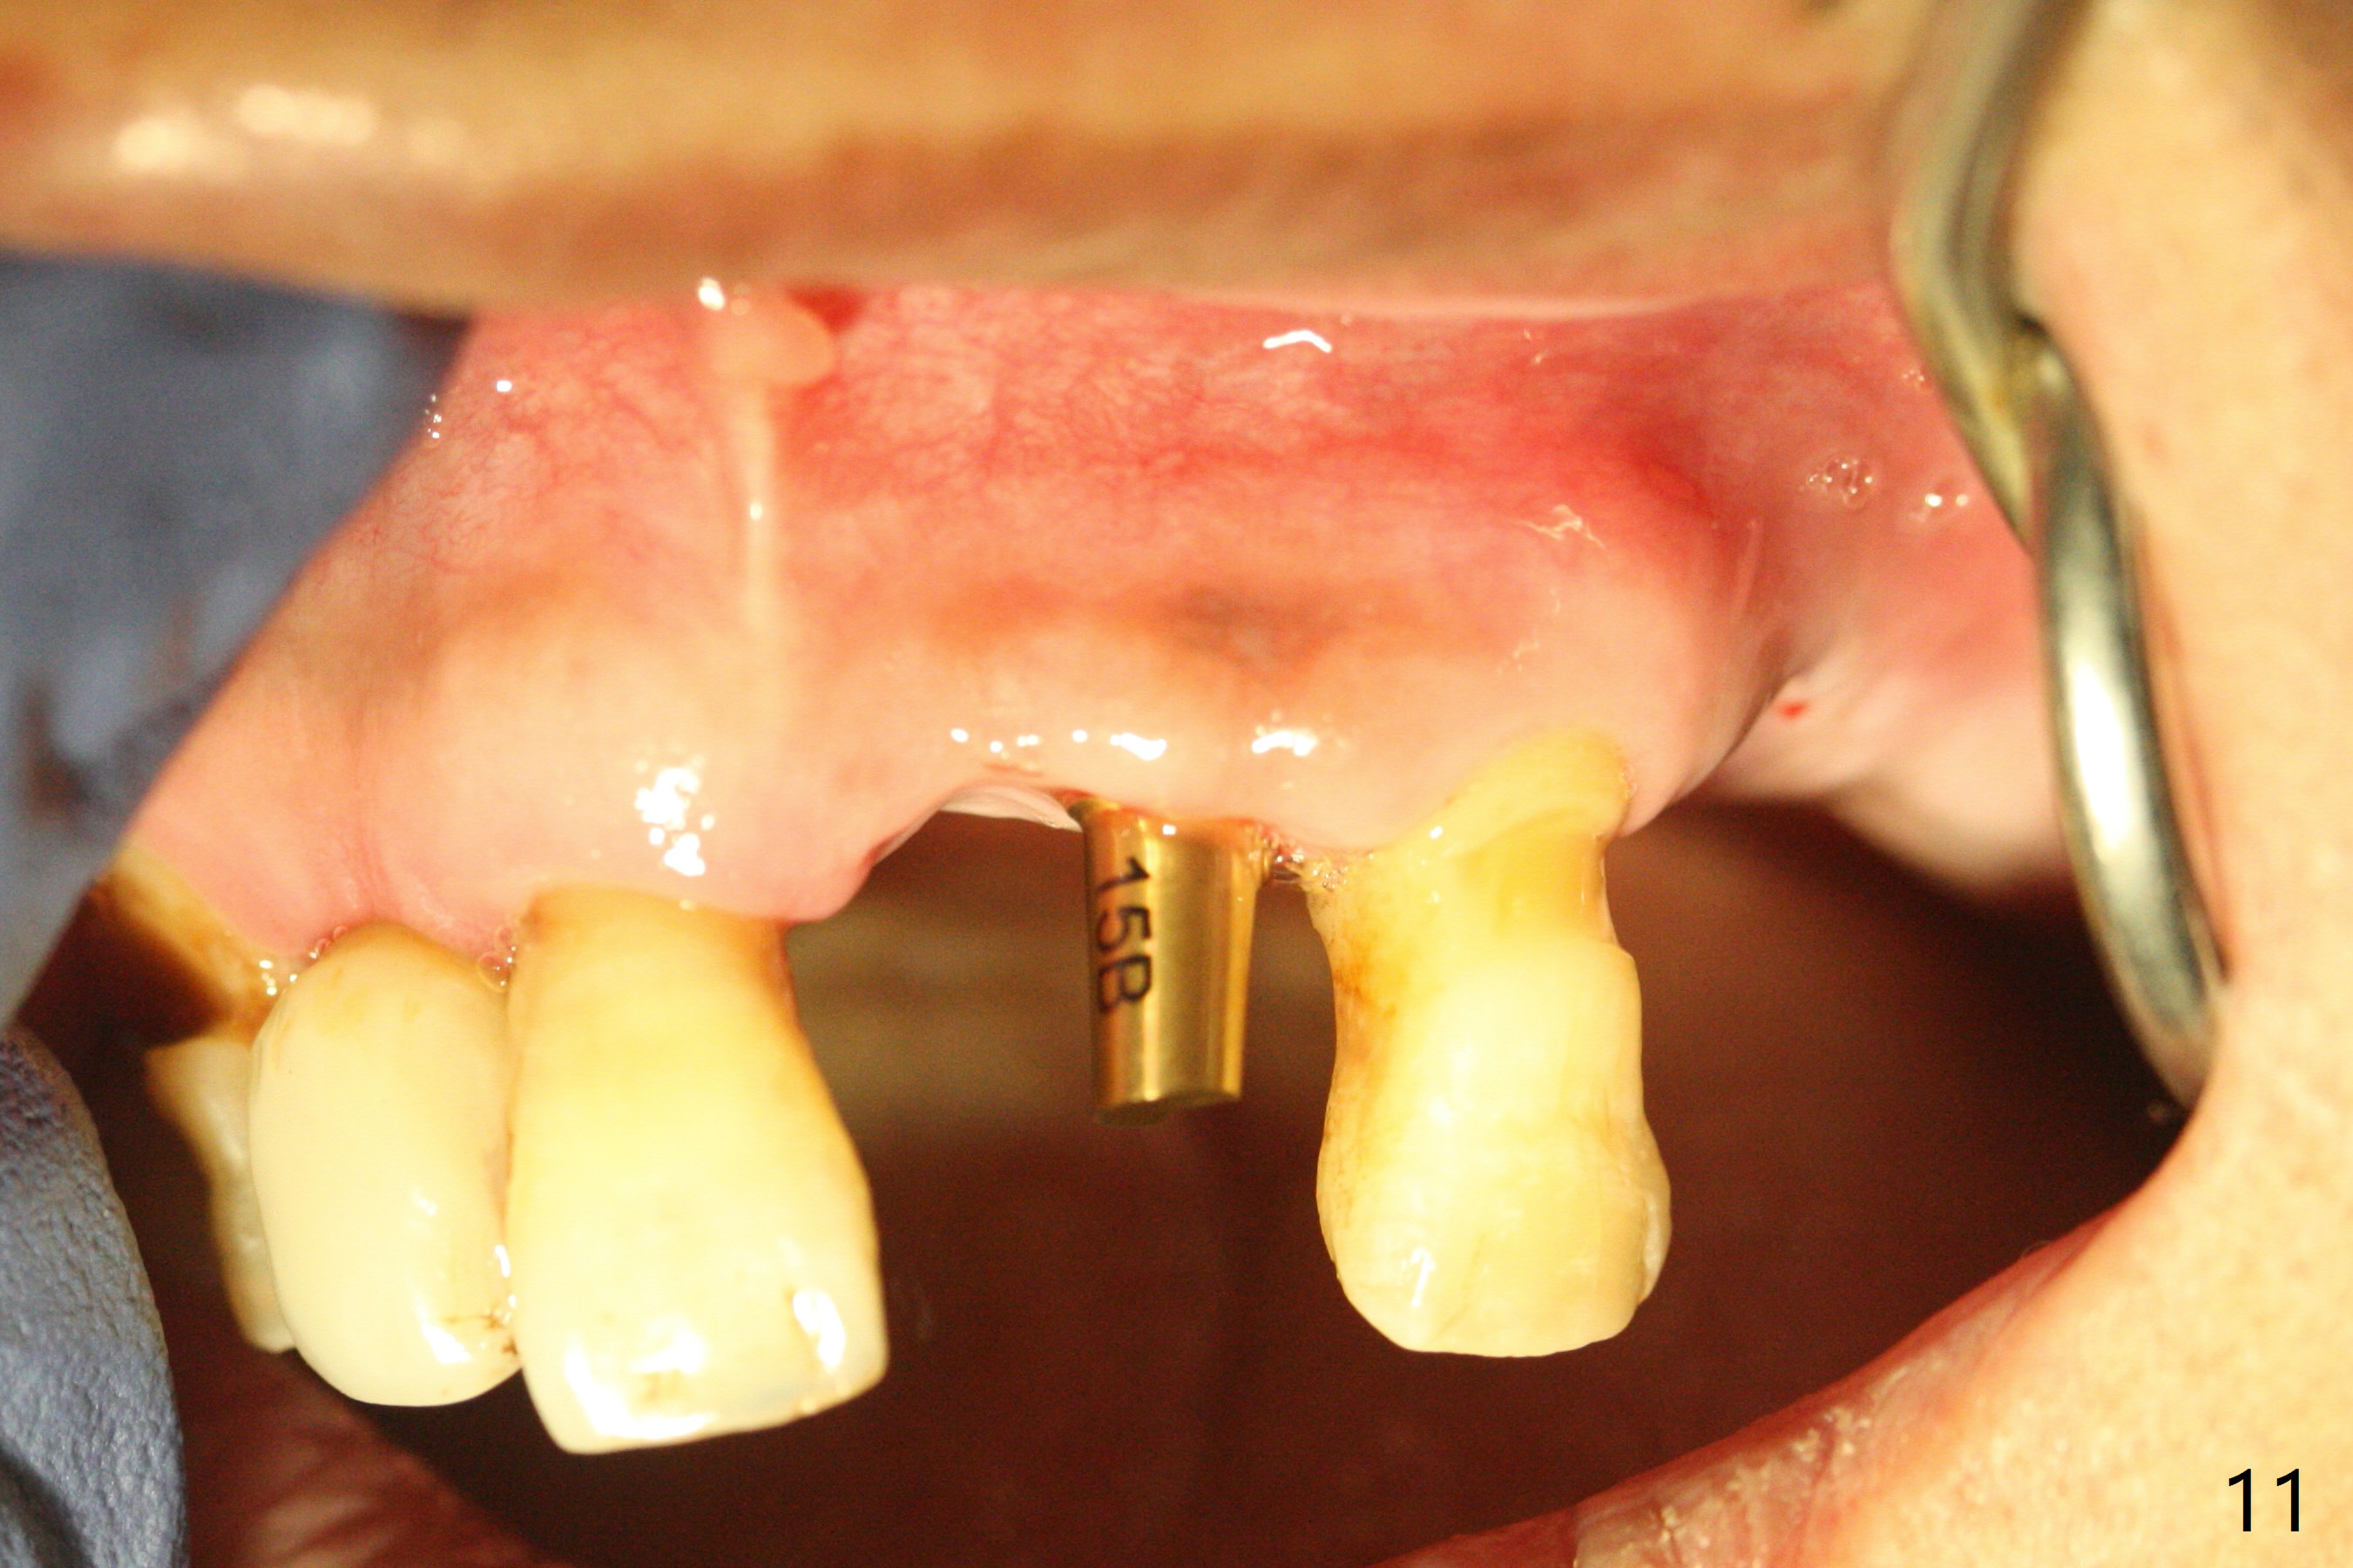

After a 4x10 mm implant is placed with fixture mounting (Fig.2 M) following sinus lift (*) at #12, osteotomy is initiated at #10 (Fig.1 (T: tube of surgical guide)). It appears that the drill (D) has good trajectory (between the Incisive Canal (red dashed line) and the canine root). The final position of the implant at #10 is acceptable (Fig.3). The implant at #12 is placed deeper (Fig.4 (arrow), as compared to Fig.2) because of clinically buccal superficial placement. The most critical challenge is anterior deep bite associated with posterior collapse. Periodontal dressing is applied. When the latter dislodges, there is minimal clearance for a provisional. Periodontal dressing is re-applied. The patient (smoker, partial edentulism with occlusal interference) returns for provisional nearly 1 month postop with chief complaint "something is lost in the back". In fact the healing abutment at #12 is lost with buccal granulation tissue (Fig.5). When a new abutment is seated, there is discomfort. When a healing screw is placed, it cannot be seated completely with two separate trials (Fig.6,7). Should we leave it as it is or open up for complete seating? It appears that the implant is loose. After preparation for clearance at #10, the abutment is retightened. It appears to turn with the underlying implant with discomfort. A 4x5 mm healing abutment is placed to reduce micro-movement. One week later, the infection at #12 dissolves with oral Amoxicillin (Fig.8). Due to limited occlusal clearance and implant tenderness when the abutment abutment is retightened, the cemented abutment is changed to a healing abutment. The implant at #10 seems to be osteointegrated, while the healing screw at #12 remains incomplete seating 3 months postop (Fig.9). The loose healing screw cannot be retightened securely, as there is bone loss around the implant 3 months postop (Fig.10 *). When a 4.5 mm x 15 degree 4 mm cuff angled abutment is placed, the mesiodistal trajectory improves (Fig.11), but there is no occlusal clearance (Fig.12). The latter would form when posterior support is established (Fig.13, either removable appliance (which the patient hates) or fixed one (finance)). Fig.14 shows the unhealed site of #12. Incision confirms the bone loss around the implant, which is removed. Although the sinus floor is absent, there is no membrane perforation. After debridement, allograft mixed with small amount of Osteogen is placed (Fig.15,16 G) and covered with Osteogen plug and 6-month membrane.